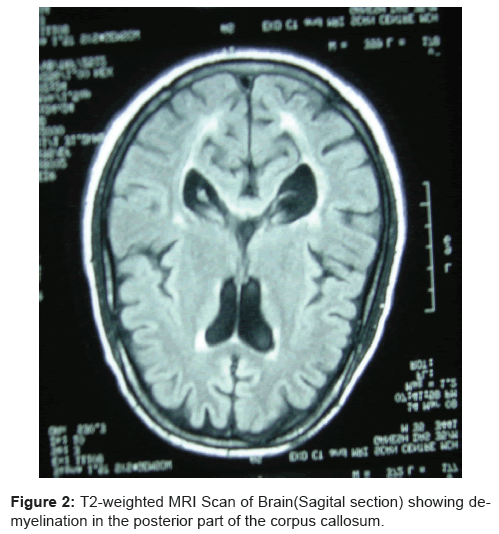

Get Demyelination Ct Brain PNG. Proposed causes for demyelination include genetics and environmental. Highly specific for atypical brain demyelination.

Of periventricular lesions would argue against a demyelinating process. This can lead to neurological problems, including slow reflexes. Ct scan of the brain was negative for any acute pathology.

Proposed causes for demyelination include genetics and environmental. When viewing a ct scan of the brain, both the brain window images and the bone window images must be viewed routinely. Brain v bone ct windows. It contains information about the normal anatomy and the different types of brain hemorrhage.